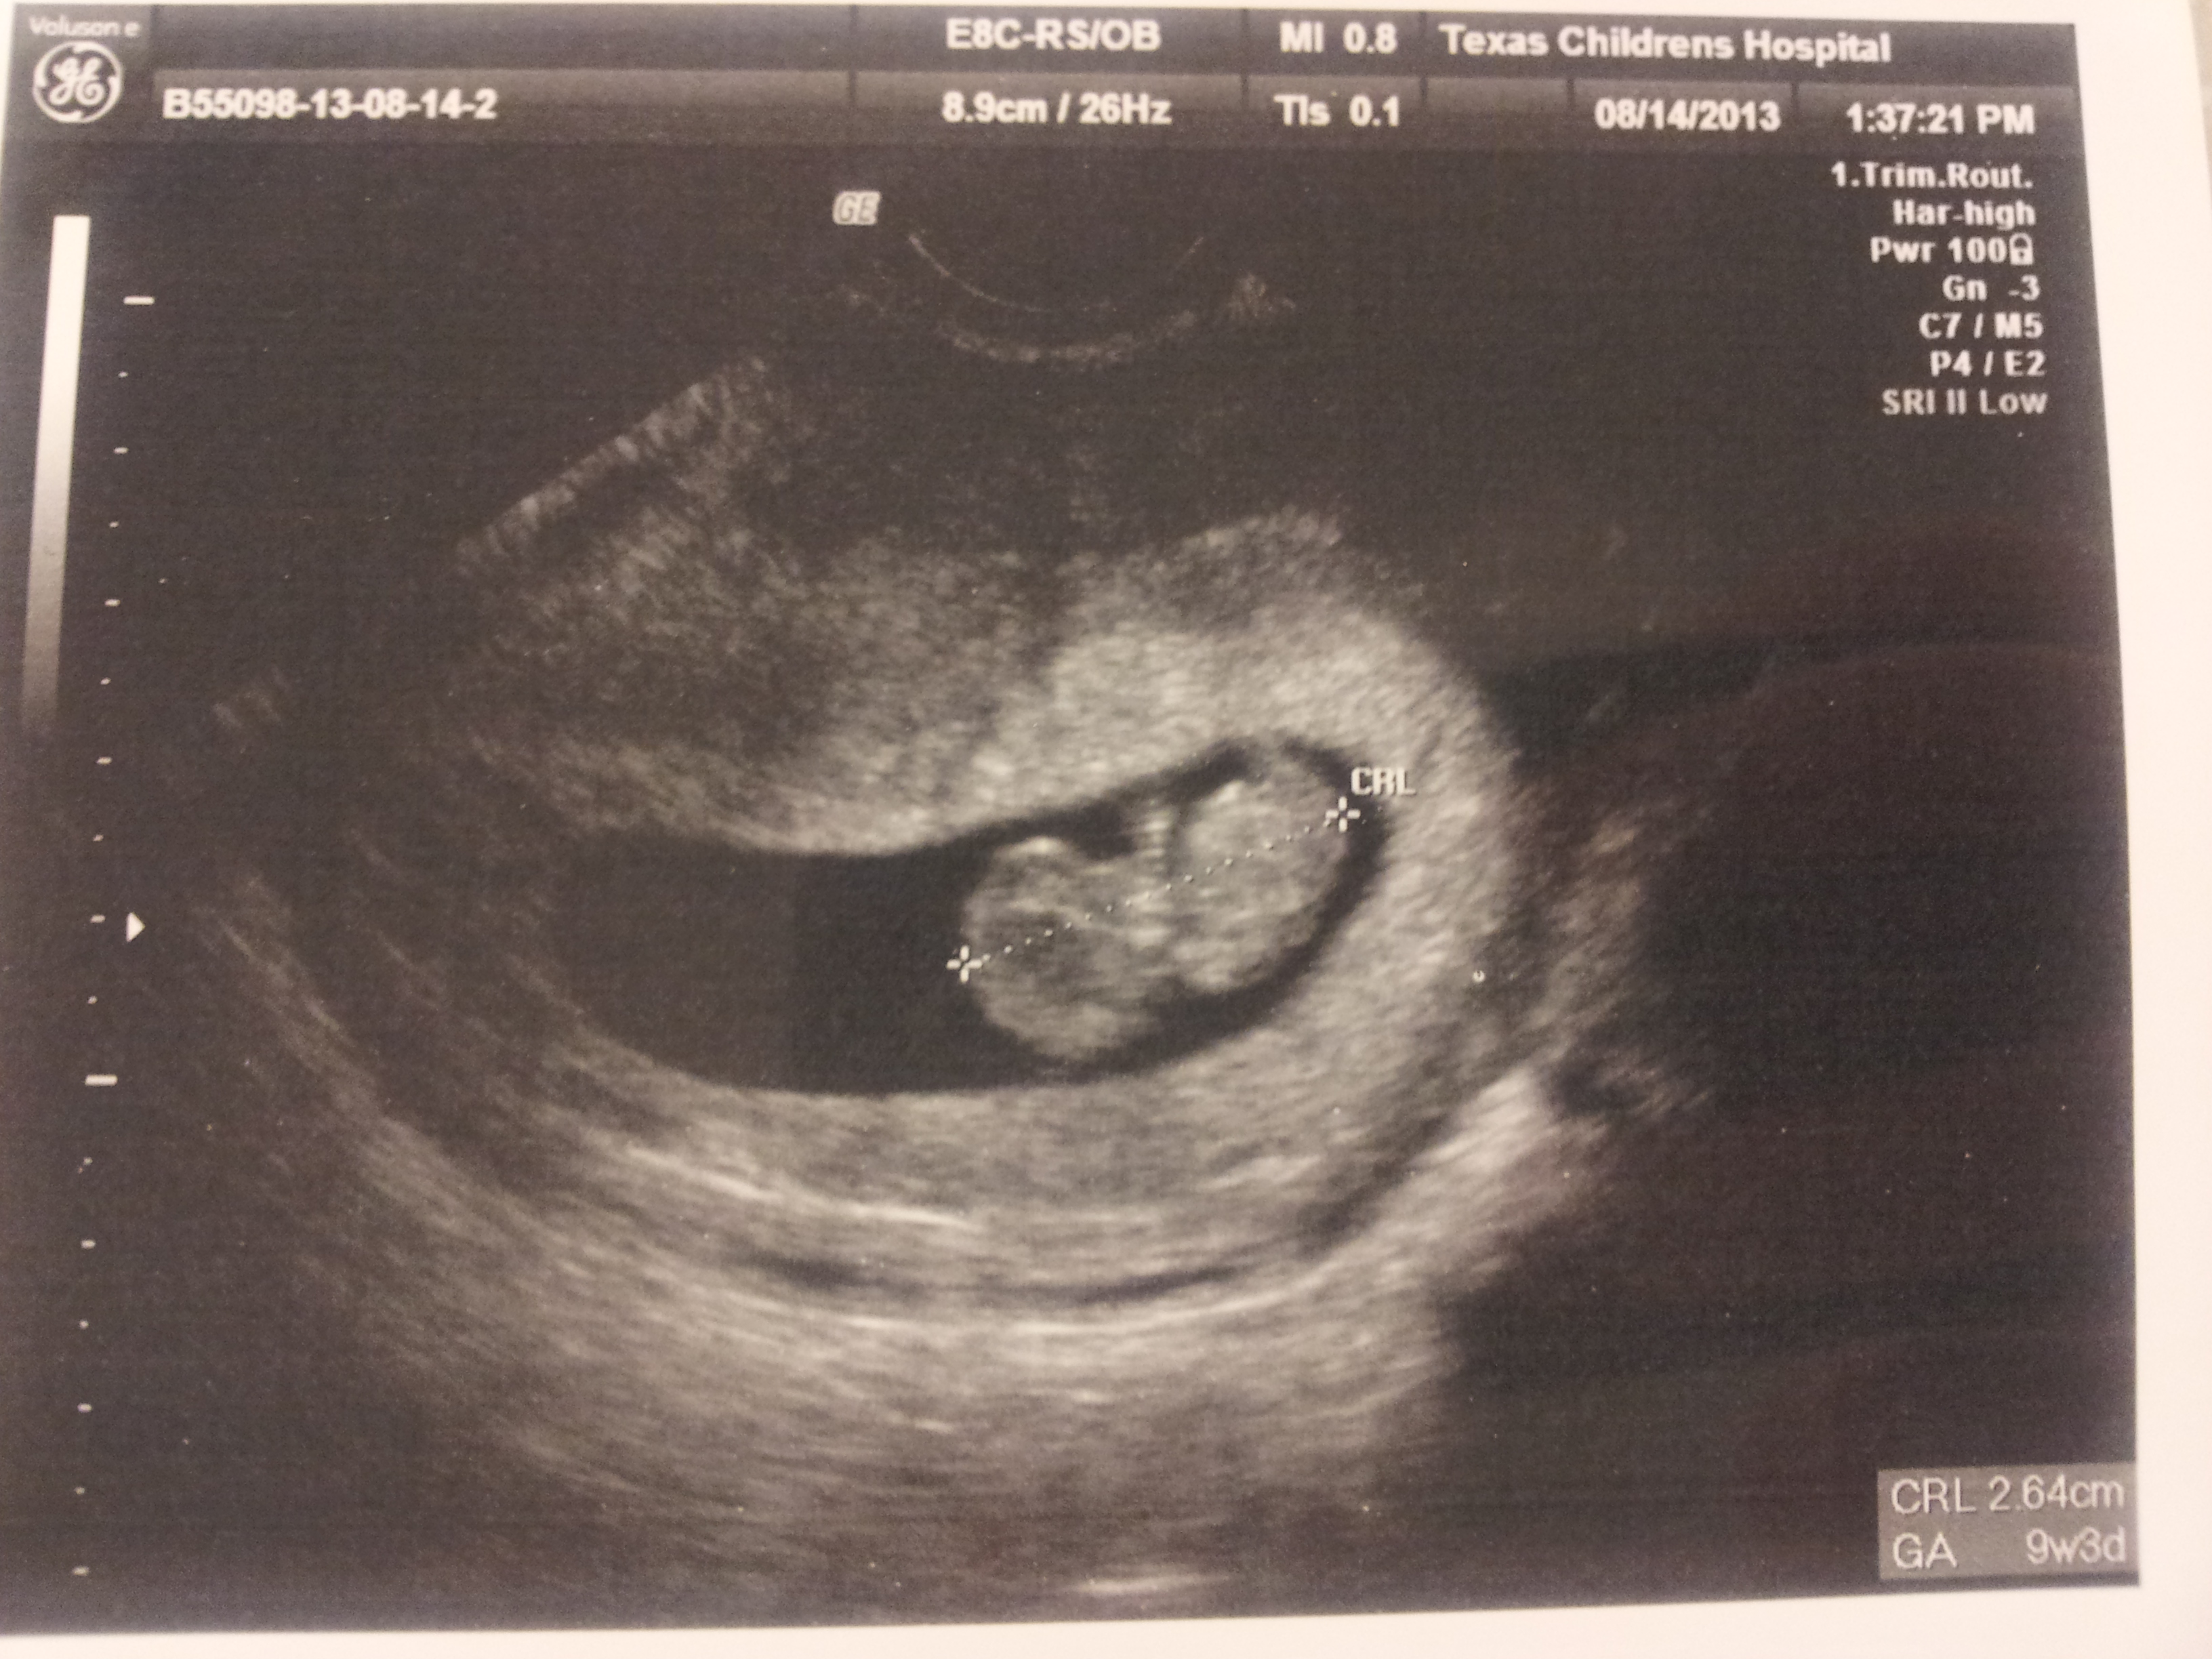

Here it is… the picture we’ve all been waiting for. Here’s a secret, don’t tell Stephanie I told you… she took another pregnancy test AFTER her original pregnancy test… just to make sure. And, I don’t even think she really thought that was all real until THIS. The picture! From what we learned today, the due date is March 16, 2014.